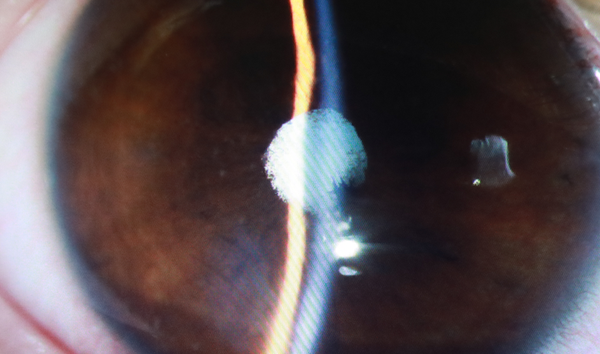

通过后续进一步检查,得知小潘患有严重葡萄膜炎,右眼并发性白内障和虹膜粘连,视力受到极大损伤。

葡萄膜炎并发症

一是葡萄膜炎形成了“并发性白内障”,本应透明的晶状体变得混浊;二是炎症导致虹膜后粘连,紧紧地贴在了晶状体前表面,三是手术后要控制炎症的发展。